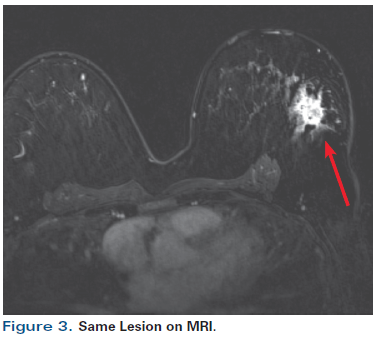

![]() Cureus Intracystic Papillary Carcinoma A Case Report | Cureus Intracystic Papillary Carcinoma A Case Report | ![]() Cureus Intracystic Papillary Carcinoma A Case Report |